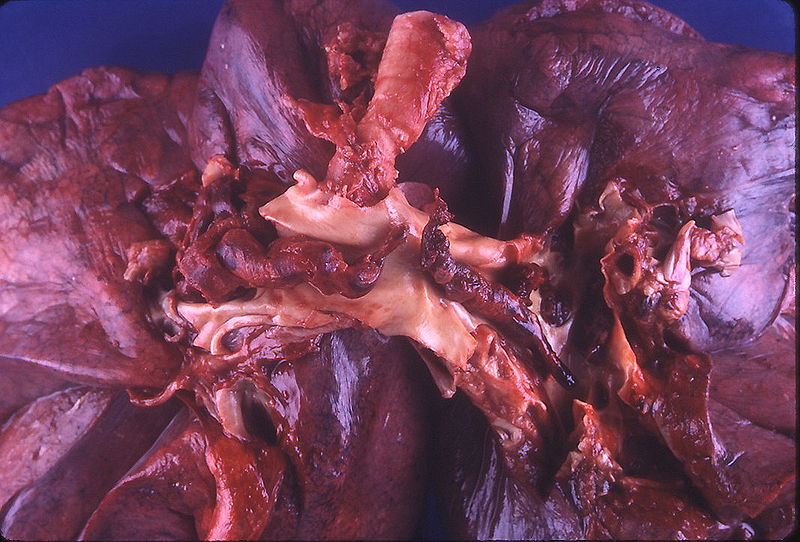

Thrombus

Ein Thrombus ist eine intravitale, pathologische Blutgerinnselmasse aus Fibrin und Blutzellen (Thrombozyten, Erythrozyten), die sich in Gefäßen oder Herzhöhlen bildet und dort haftet.

Histologie

• Charakteristische Zahn-Linien: Wechselnde Schichten aus Thrombozyten/Fibrin und Erythrozyten.

• Kann Leukozyten und nekrotisches Material enthalten.

Typen & Lokalisation

• Arteriell (weiß): Thrombozyten-/fibrinreich; hoher Blutfluss, Endothelschaden (z.B. Koronararterien).

• Venös (rot): Erythrozyten-/fibrinreich; Blutstase (z.B. tiefe Venenthrombose (TVT)).

• Herzthrombus: In Herzhöhlen (z.B. bei Vorhofflimmern, nach Myokardinfarkt).